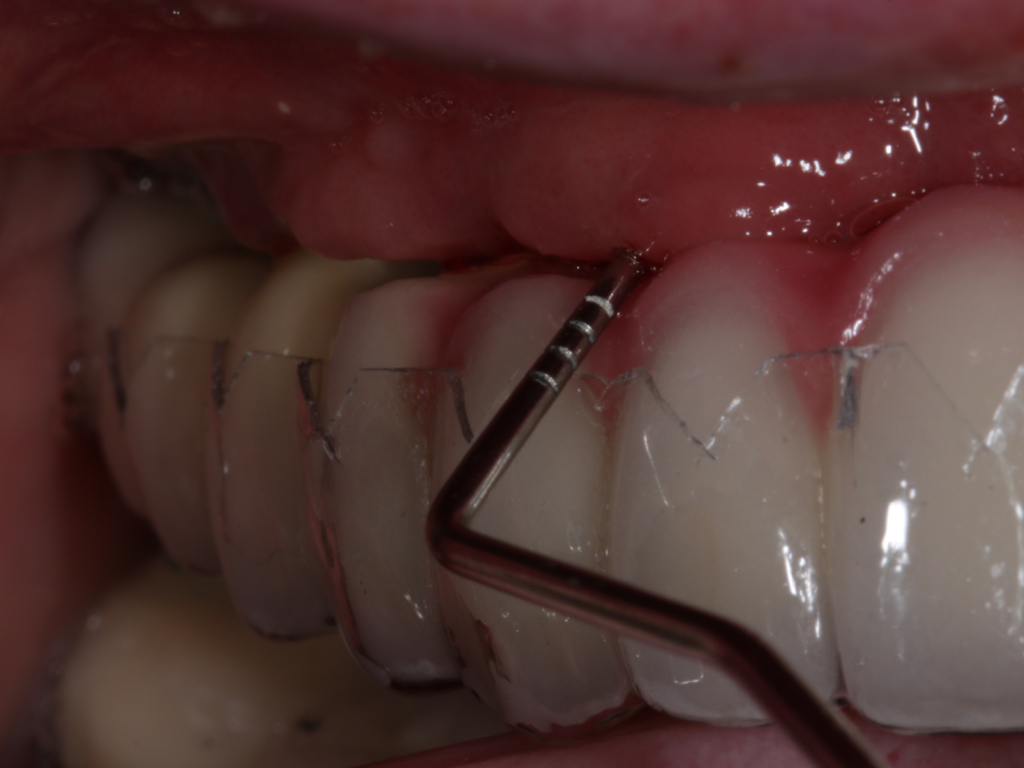

Fig 7. Probing of the buccal surface reveals additional loss of attachment around the dental implant.

Fig 8. Flap elevation confirms circumferential bone loss.

Probing is useful to determine the presence of biological complications at the buccal and lingual sites of implants, which cannot be evaluated on a radiograph (Figure 6 through Figure 8). Because of the absence of a periodontal ligament, bone loss on the buccal and lingual aspects of an implant indicates loss of support for the implant and may be a sign of additional circumferential bone loss around the implant.35